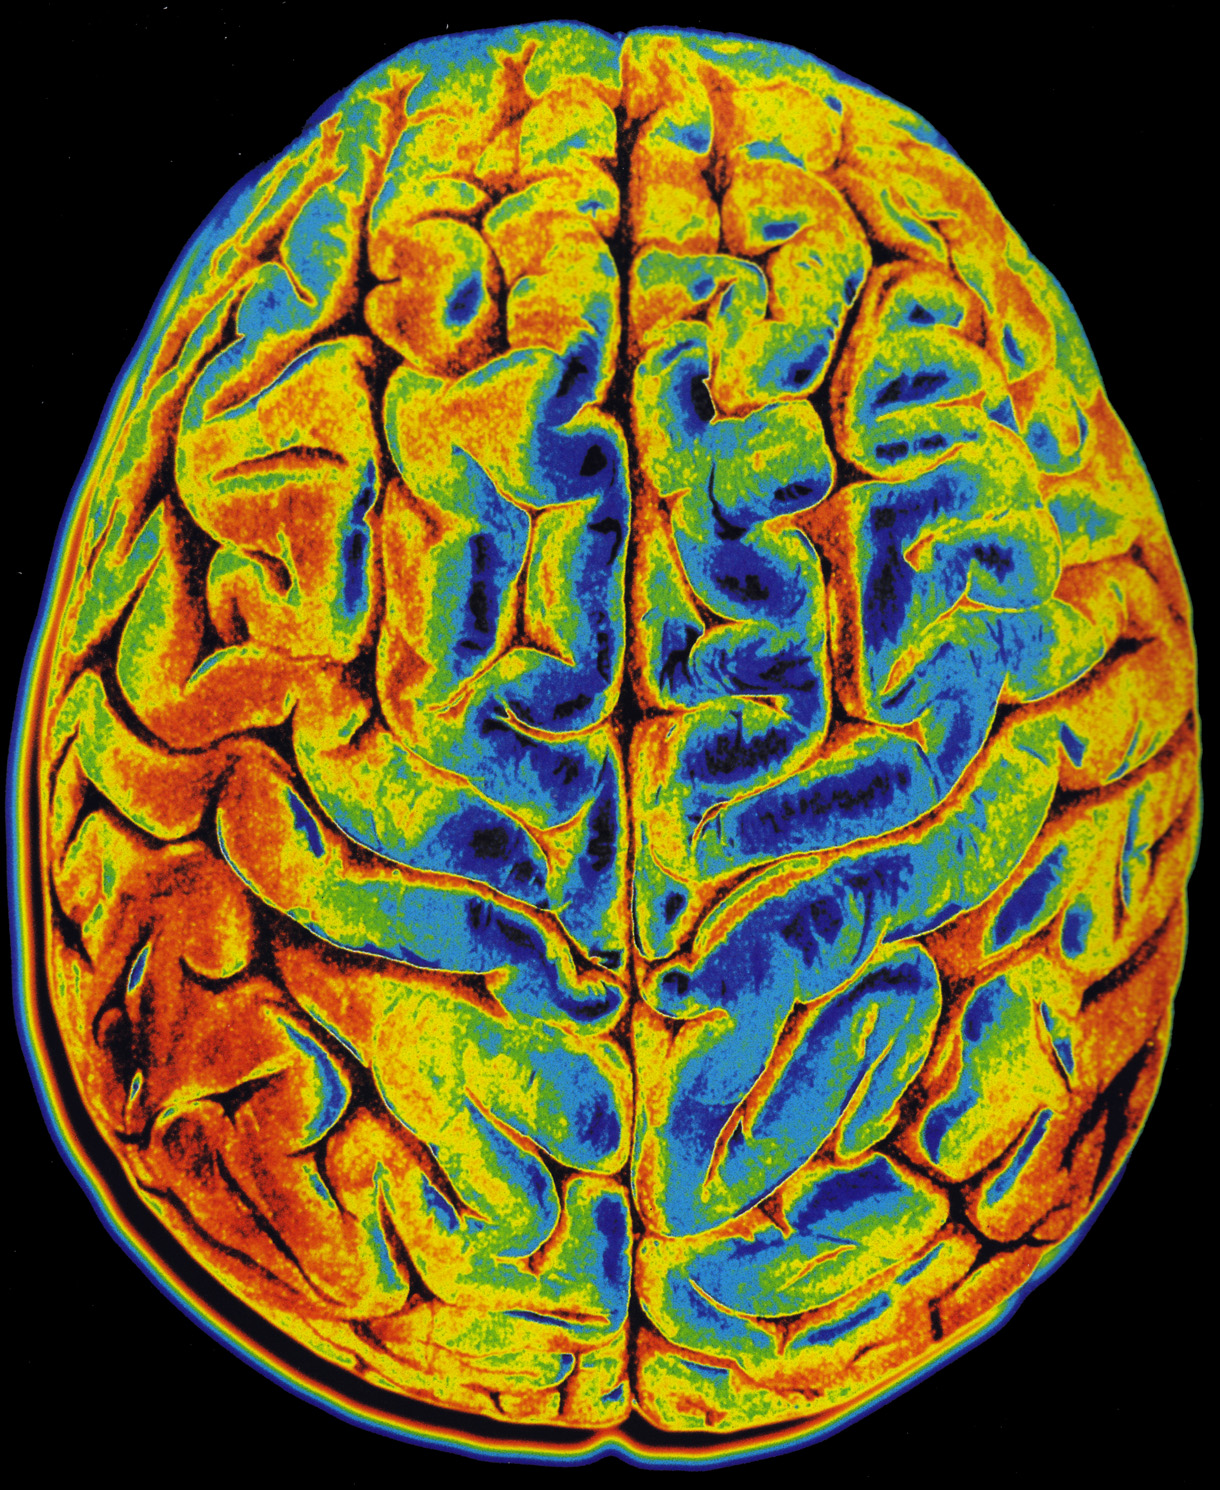

Human Brain Scan - Stock Image - F021/3614 - Science Photo Library

www.sciencephoto.com

www.sciencephoto.com

scan brain human